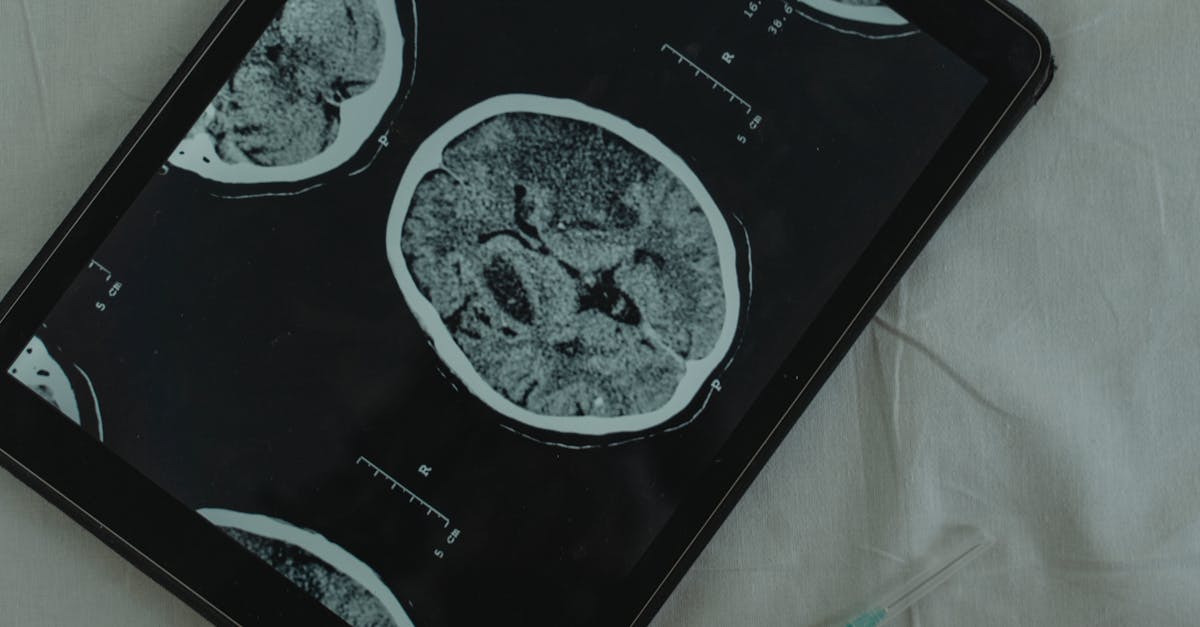

Unilateral weakness, characterized by reduced strength on one side of the body affecting both arm and leg, represents one of the most recognizable and urgent neurological presentations requiring immediate evaluation. This asymmetry typically manifests as a dramatic difference in motor function between the affected and unaffected sides, with patients experiencing difficulty lifting, gripping, or coordinating movements on the weakened side. The weakness often follows specific patterns depending on the location of the neurological lesion—upper motor neuron lesions typically present with weakness that is more pronounced in the extensors of the upper extremity and flexors of the lower extremity, while lower motor neuron lesions may show more focal patterns of weakness. Stroke remains the most common cause of acute unilateral weakness, with the pattern and severity often correlating with the vascular territory affected and the extent of brain tissue damage. However, other conditions such as brain tumors, traumatic brain injury, multiple sclerosis exacerbations, or even complex migraines can present with similar asymmetrical weakness patterns. The critical nature of this presentation lies in the time-sensitive treatment options available for acute stroke, where interventions such as thrombolytic therapy or mechanical thrombectomy can dramatically improve outcomes when administered within specific time windows. Recognition of unilateral weakness should trigger immediate activation of emergency medical services and rapid transport to a stroke-capable facility for comprehensive neurological evaluation and potential intervention.

Asymmetrical coordination deficits, where one limb demonstrates significantly impaired fine motor control, balance, or smooth movement execution compared to the contralateral limb, often indicate pathology affecting the cerebellum, brainstem, or their connecting pathways. These deficits typically manifest as difficulties with precise movements, such as finger-to-nose testing, rapid alternating movements, or heel-to-shin coordination, with the affected limb showing tremor, dysmetria (overshooting or undershooting targets), or dysdiadochokinesia (inability to perform rapid alternating movements smoothly). Cerebellar strokes, particularly those affecting the superior cerebellar artery territory, can cause dramatic unilateral coordination deficits that may initially be mistaken for weakness but are actually due to disrupted motor planning and execution. Multiple sclerosis frequently causes asymmetrical cerebellar symptoms, with patients experiencing coordination difficulties that may fluctuate in severity and can significantly impact activities of daily living such as writing, eating, or walking. Brain tumors affecting the cerebellum or brainstem can also present with progressive asymmetrical coordination deficits, often accompanied by other neurological signs such as cranial nerve abnormalities or altered consciousness. The assessment of coordination asymmetries requires systematic testing of appendicular and axial coordination, including evaluation of gait, stance, and fine motor tasks under various conditions. Magnetic resonance imaging of the brain with particular attention to the posterior fossa structures is often necessary to identify structural causes of coordination deficits, while laboratory studies may help identify inflammatory or metabolic causes of cerebellar dysfunction that require specific treatment approaches.

Asymmetrical deep tendon reflexes between corresponding limbs serve as fundamental indicators of nervous system pathology and provide crucial information for differentiating between upper motor neuron, lower motor neuron, and mixed neurological conditions. Hyperreflexia on one side compared to the other typically suggests upper motor neuron pathology affecting the corticospinal tract, with conditions such as stroke, spinal cord compression, or multiple sclerosis commonly causing these asymmetrical presentations. The presence of pathological reflexes such as the Babinski sign, Hoffman's reflex, or sustained clonus on the hyperreflexic side further supports upper motor neuron involvement and may indicate the need for urgent neuroimaging to identify potentially treatable causes such as spinal cord compression or brain lesions. Conversely, asymmetrically diminished or absent reflexes suggest lower motor neuron pathology, peripheral neuropathy, or radiculopathy affecting the reflex arc components including sensory nerves, spinal cord segments, motor neurons, or peripheral motor nerves. Radiculopathy often presents with specific patterns of reflex loss corresponding to the affected nerve root levels—for example, C5-C6 radiculopathy may cause diminished biceps and brachioradialis reflexes, while L4 radiculopathy may affect the patellar reflex. The evaluation of reflex asymmetries requires systematic testing of all major deep tendon reflexes using consistent technique and grading scales, with attention to both the presence and quality of the reflex response. Electromyography and nerve conduction studies can help differentiate between various causes of reflex abnormalities, while magnetic resonance imaging of the brain or spine may be necessary to identify structural causes of upper motor neuron signs that require specific interventions.